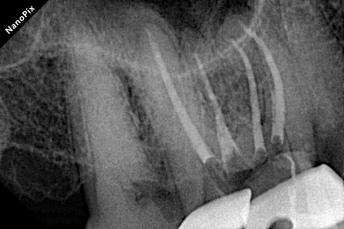

Shaping with Perfection: The canals were shaped using the DENCO Only One File Blue (up to 40.06). The file navigated the extreme curvatures and calcifications flawlessly without any transportation.

Showcasing perfectly tapered and centered canal preparations.

Confirming the dense, 3D fill of the entire root canal system.

Displaying the excellent final result, particularly highlighting the beautiful flow in the mesiobuccal root canals